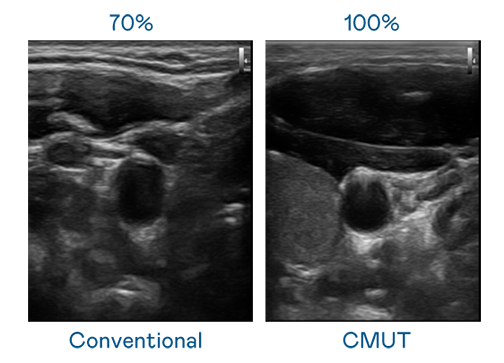

CMUT 技术是一种用电容式微机电元件来产生超音波讯号的技术。与传统 PZT 压电式技术相比,CMUT 频宽增加 30%,更宽频的超音波讯号让影像解析度大幅提升,是实现高影像品质医疗超音波扫描、促进精准医疗发展的关键技术。

超音波影像的解析度高低,首先取决于探头能发出的讯号频宽。AGGAME CMUT 可提供高清晰的超音波讯号,提供高频宽、高灵敏度、影像纹理细节更高的超音波影像,协助医护人员缩短影像判读时间及利用精准的医疗影像进行诊断。